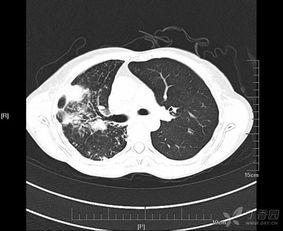

首先,肺功能是评估呼吸系统疾病的重要手段。比如,慢性阻塞性肺疾病(COPD)、哮喘等疾病,都会对肺功能造成影响。通过肺功能检测,医生可以判断病情的严重程度,制定合理的治疗方案。

视频还会介绍一些常见的呼吸系统疾病,如COPD、哮喘等,以及这些疾病对肺功能的影响。这样,你就能更好地了解自己的健康状况,预防疾病的发生。